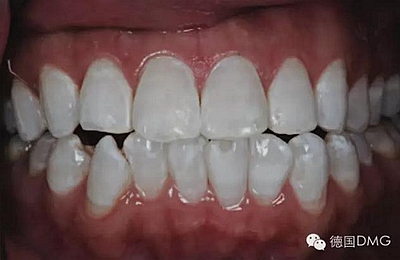

一28歲女性患者來我院修復(fù)科就診,主訴為前牙嚴(yán)重的牙齒著色和缺損十余年,要求改善牙齒的美觀。臨床檢查表明該患者有重度氟斑牙,極大的影響了前牙美學(xué)。

考慮到患者為年輕人,保守治療方法比傳統(tǒng)侵入性治療手段更為合適。術(shù)前牙周治療預(yù)防牙齦炎癥和改善牙齦健康狀態(tài),隨后聯(lián)合采用釉質(zhì)打磨、牙漂白和樹脂滲透來處理牙釉質(zhì)表面。

5、由于氟斑牙存在釉質(zhì)礦化不全等問題,家庭漂白兩周后,使用標(biāo)準(zhǔn)的樹脂滲透技術(shù) (Icon, DMG Products, Hamburg. Germany) 來預(yù)防釉質(zhì)齲。最后,徹底改變患者的前牙美學(xué),并在一年后仍保持穩(wěn)定。

利用釉質(zhì)打磨技術(shù)聯(lián)合牙齒漂白和樹脂滲透技術(shù)的微創(chuàng)方法是治療重度氟斑牙的有效方式。同時(shí),這一技術(shù)費(fèi)用低、省時(shí)間。